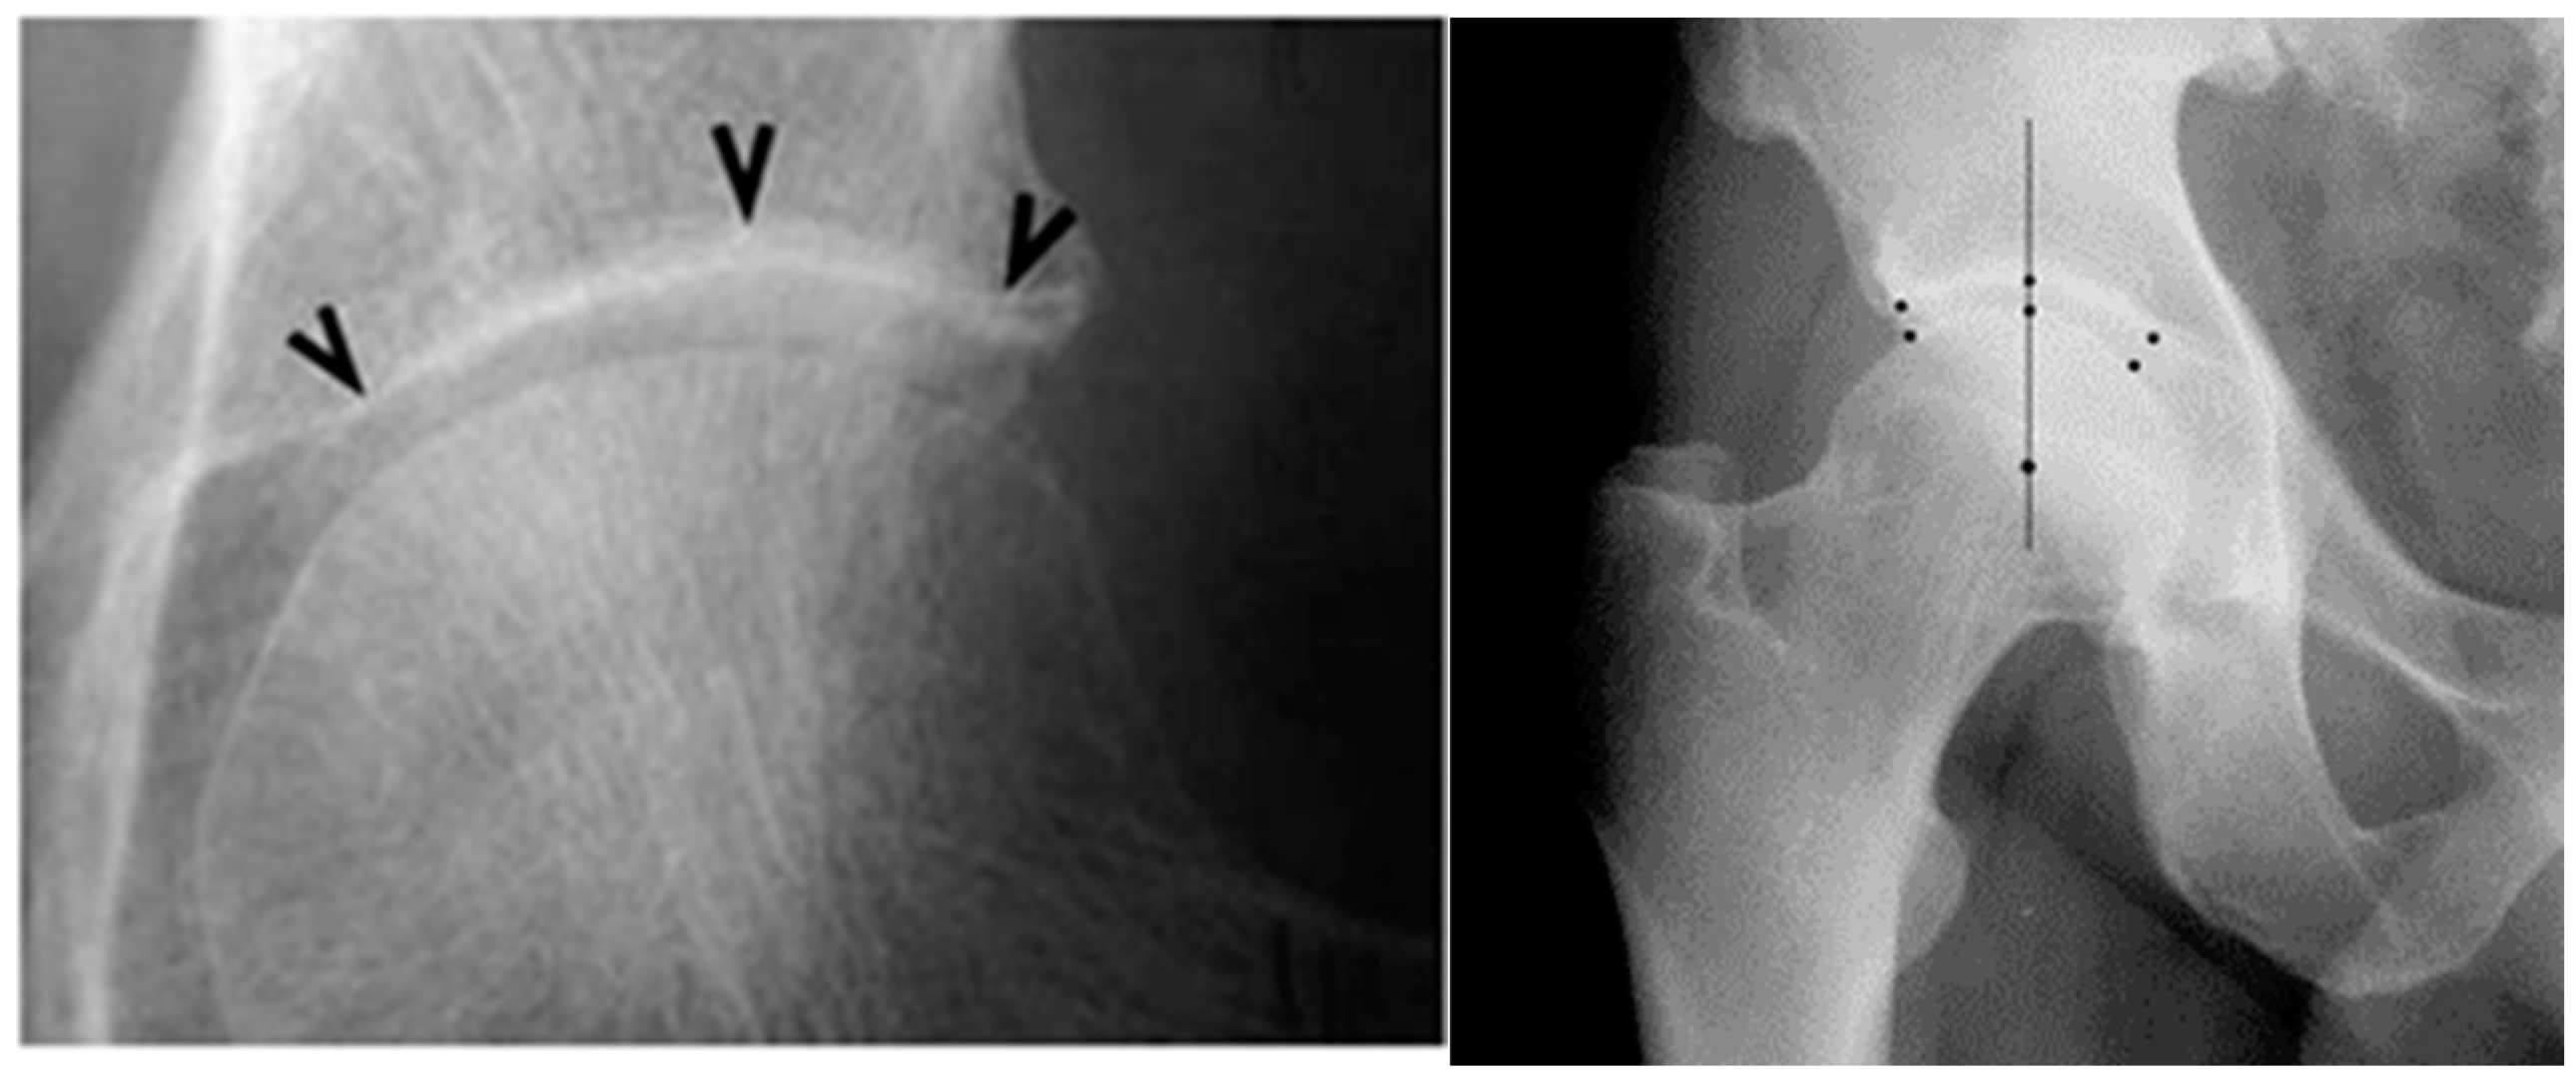

- Ledingham, J.; Dawson, S.; Preston, B.; Milligan, G.; Doherty, M. Radiographic patterns and associations of osteoarthritis of the hip. Ann. Rheum. Dis. 1992, 51, 1111–1116. [Google Scholar] [CrossRef] [PubMed]

- Conrozier, T.; Merle-Vincent, F.; Mathieu, P.; Richard, M.; Favret, H.; Piperno, M.; Caton, J.; Vignon, E. Epidemiological, clinical, biological and radiological differences between atrophic and hypertrophic patterns of hip osteoarthritis: A case-control study. Clin. Exp. Rheumatol. 2004, 22, 403–408. [Google Scholar] [PubMed]

- Schnitzler, C.M.; Mesquita, J.M.; Wane, L. Bone histomorphometry of the iliac crest, and spinal fracture prevalence in atrophic and hypertrophic osteoarthritis of the hip. Osteoporos Int. 1992, 2, 186–194. [Google Scholar] [CrossRef] [PubMed]